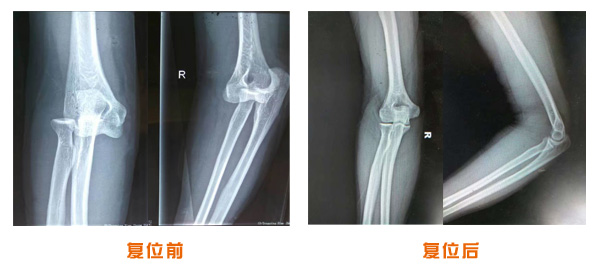

肥城市安駕莊梁氏骨科醫(yī)院是一所以梁氏手法正骨配合膏藥為特色的現(xiàn)代化專科醫(yī)院。

梁氏骨科術(shù)始創(chuàng)于清雍正年間,歷經(jīng)八代,至今已有三百年歷史。據(jù)1929年泰安縣志載“梁瑞圖先生,字增生,號蓮峰,安駕莊人,精岐黃并發(fā)明接骨,凡跌打車凡跌打車軋皮不破而碎骨者......【詳細】 |